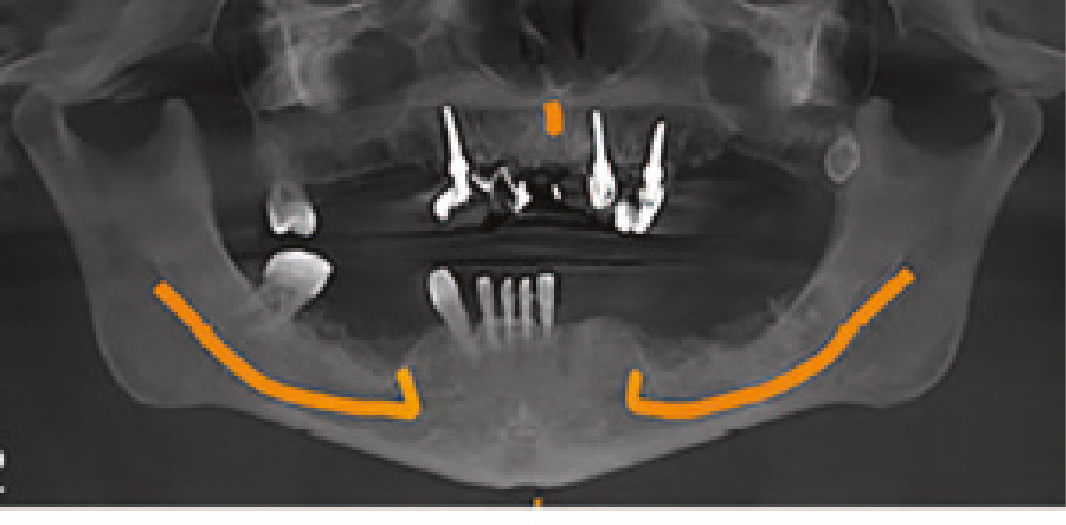

Рис. 2 Дооперационная ОПТГ, клинический случай 1

Клиническое применение классификации «ABCD» Следующие клинические случаи покажут применение этой классификации. Первый случай – молодая пациентка с адентией (Рисунки со 2 по 8), потерявшая все зубы из-за пародонтита.

• A: A1 (40 лет),

• B: B2,

• C: C3,

• D: D2,

оставляет нам 14 мм межокклюзионное пространство.

С учетом возраста пациентки для протеза требовалось долгосрочное функционирование. В этом случае применялись 7 имплантатов в каждой арке для поддержки закрепленного на винтах металлокерамического протеза. Также у пациентки была высокая линия улыбки (C3), и альвеолярный гребень виден в максимальной позиции улыбки. Во время хирургической операции было запланировано рассечение альвеолярного гребня, чтобы скрыть линию перехода после обеспечения достаточного объема костной ткани (B2) для установки гребневых имплантатов в области передних зубов. Соединение белого и розового в протезе было обработано соответствующим образом, чтобы сделать его более приемлемым для молодой пациентки. Боковой участок верхней челюсти был трансплантирован для увеличения объема костной ткани.